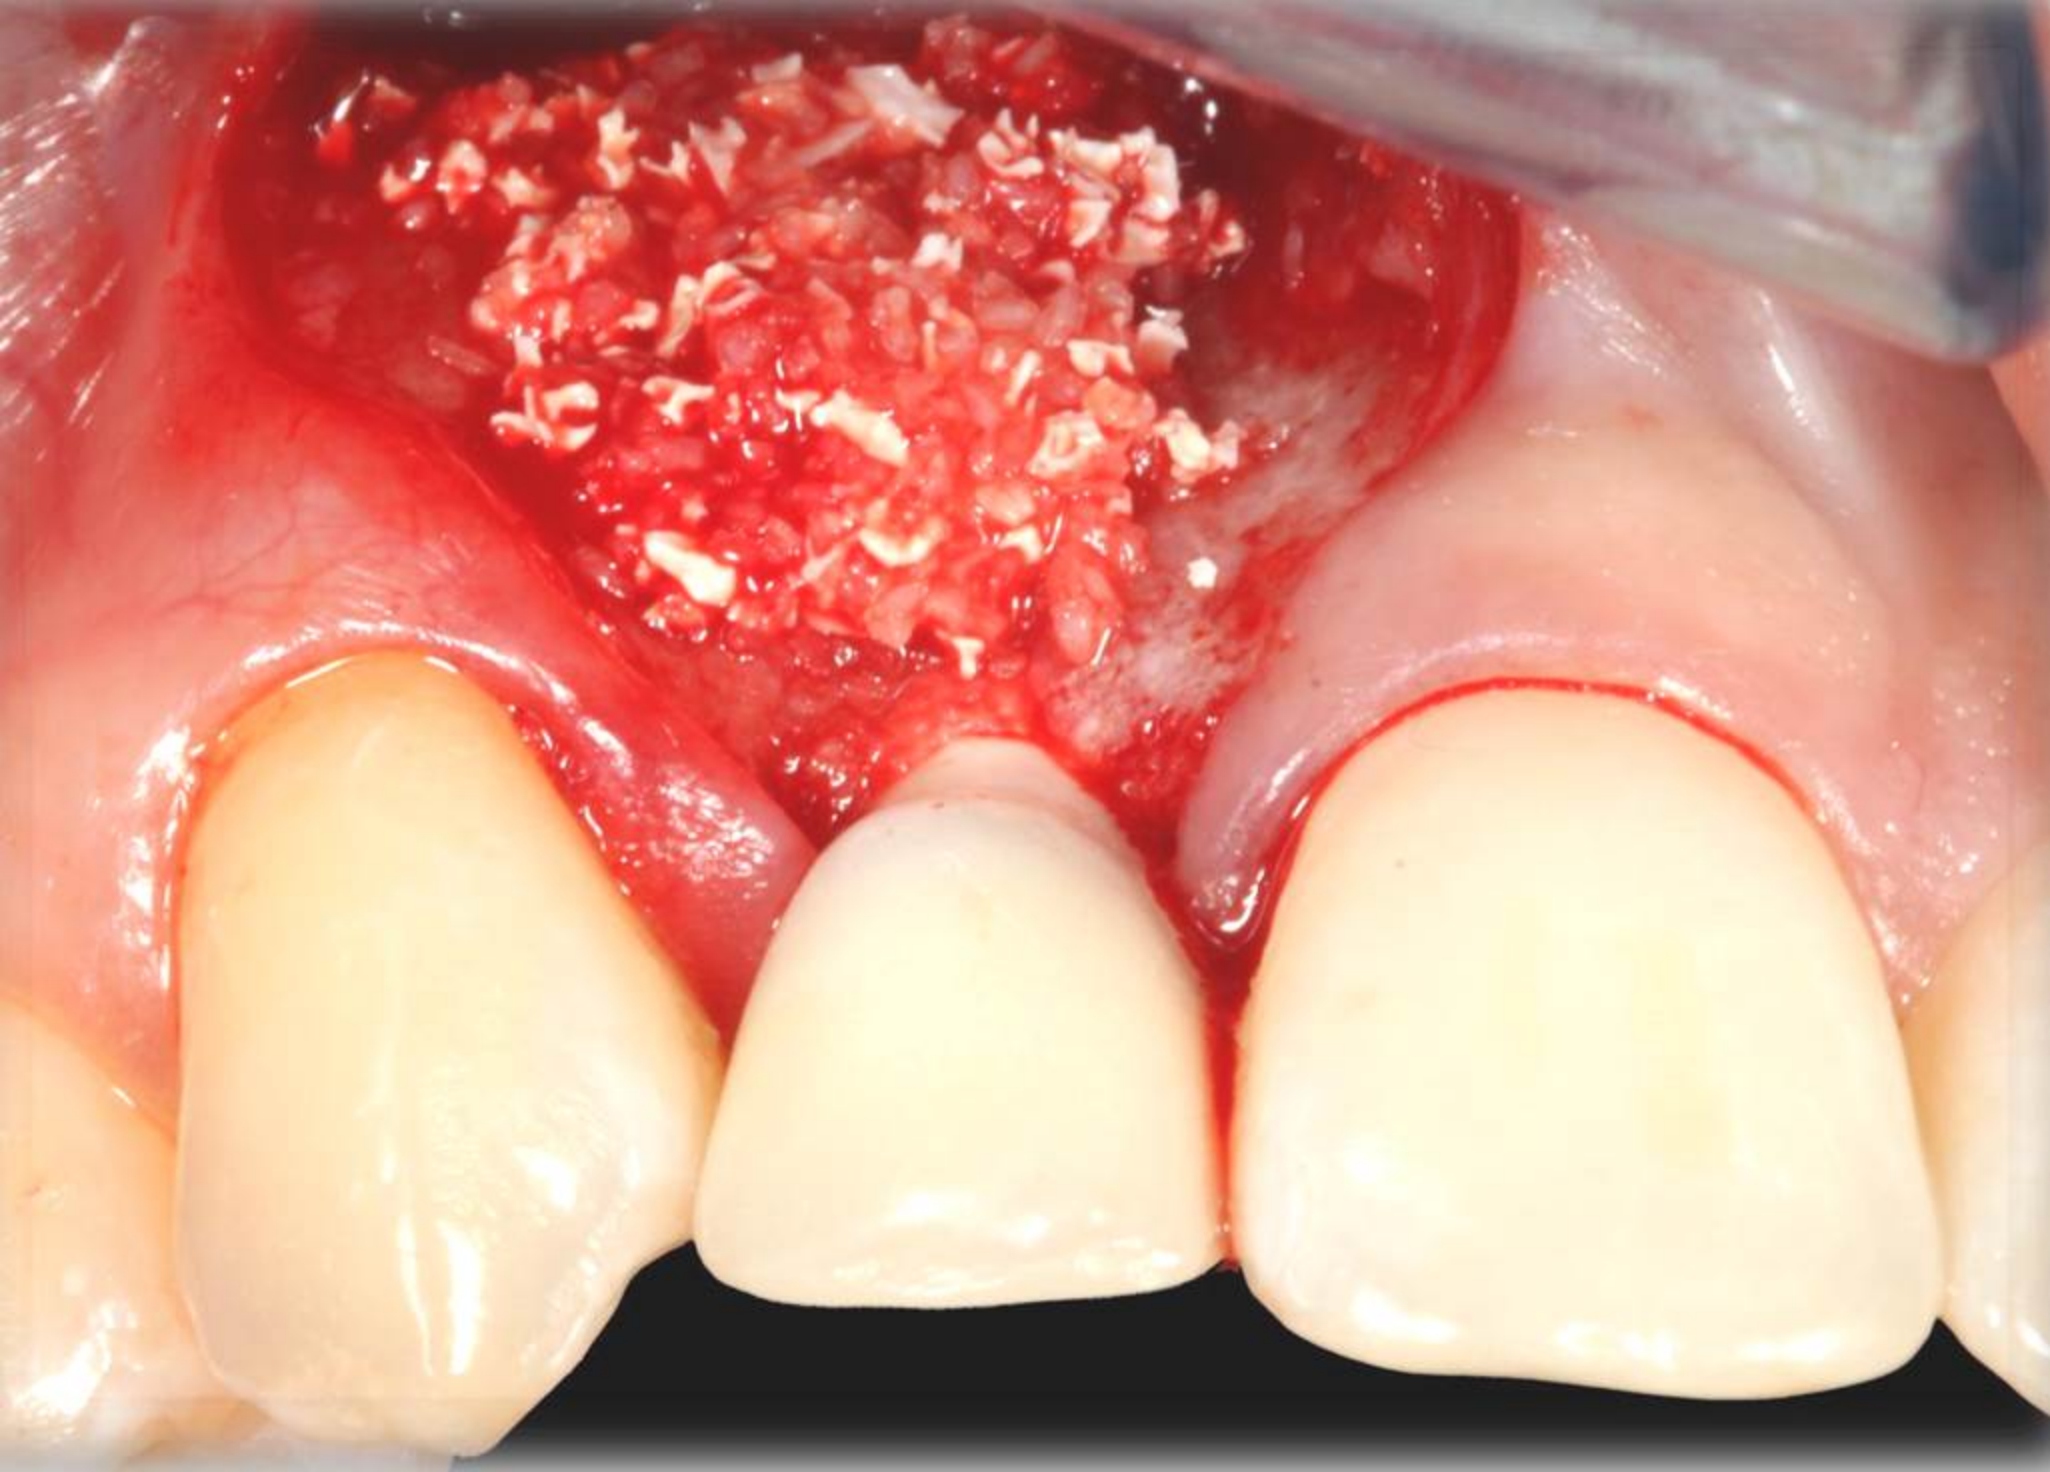

Fig 15. A temporary abutment and crown were inserted. A bone graft was then placed on the buccal aspect to augment the thin buccal bony plate.

Figure 15